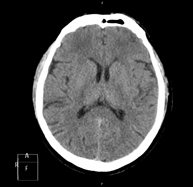

- TC Crani

Prova radiològica que consisteix en obtenir imatges del crani d'alta definició anatòmica (tronc cerebral, cerebel, cervell, calota cranial, etc. ) mitjançant l'ús d'un equip de TC (Tomografia Computeritzada). Indicacions: traumatismes, cefalea, trastorns de la memòria, pèrdua de força sobtada en una extremitat o meitat del cos. - TC Coll